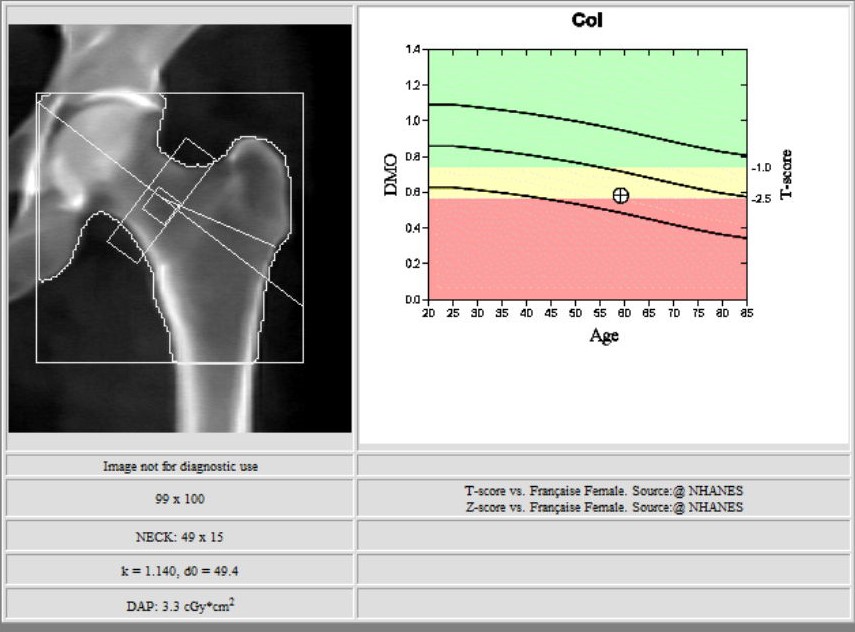

L’ostéodensitométrie mesure précisément la densité osseuse au niveau de deux sites principaux (souvent le rachis lombaire et le col fémoral), grâce à une technique dite biphotonique utilisant deux faisceaux de rayons X à très faible dose.

Elle constitue aujourd’hui la méthode la plus précise et la plus fiable pour diagnostiquer l’ostéoporose et évaluer le risque de fracture.

Les deux zones habituelles analysées sont :

2. la hanche.

Elles permettent une estimation fiable du risque fracturaire.